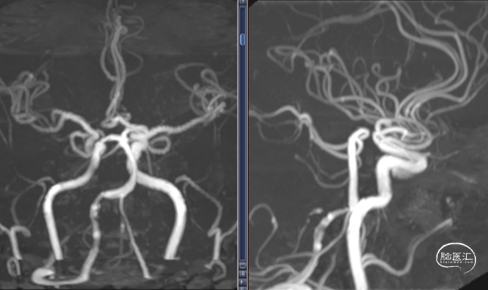

临床随访:

术后3个月门诊复查,恢复良好,无头痛及认知功能障碍,已恢复正常工作。头颅CT正常,无脑积水表现。MRA显示椎动脉血流通畅,无明显复发。

术后12个月复查DSA,右椎动脉术后改变,无复发。停用阿司匹林。